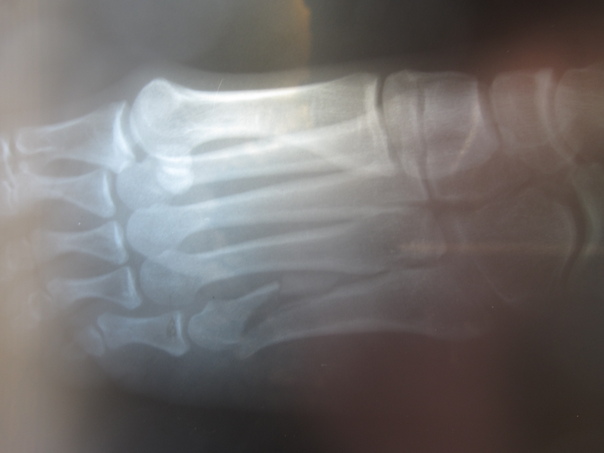

![]() Liz's Dancer's Fracture Los Angeles, CA While Liz was rehearsing for a performance she was going to be doing, she apparently jumped and landed wrong on her foot. We really didn't think it was broken for the first two days, but after ice baths and compression wouldn't heal it, I took her to a doctor to have it X-rayed. Sure enough she had what they refer to as a Dancer's Fracture, or a break along the 5th metatarsal in the foot. To make matters worse, the doctor said it would need to be operated on right away and would likely need a screw put into it to hold it together. Liz's mom came in town and handled most of the matter for her. I was happy to share in her pain medication with her! In this album: Dancer's Fracture |

Dancer's Fracture